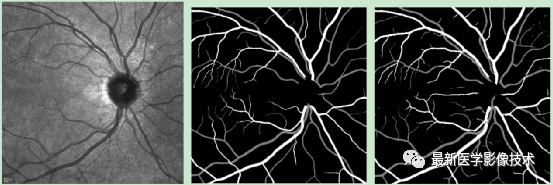

4、验证集分割结果,左图是眼底图像,中间是金标准图像,右图是分割图像